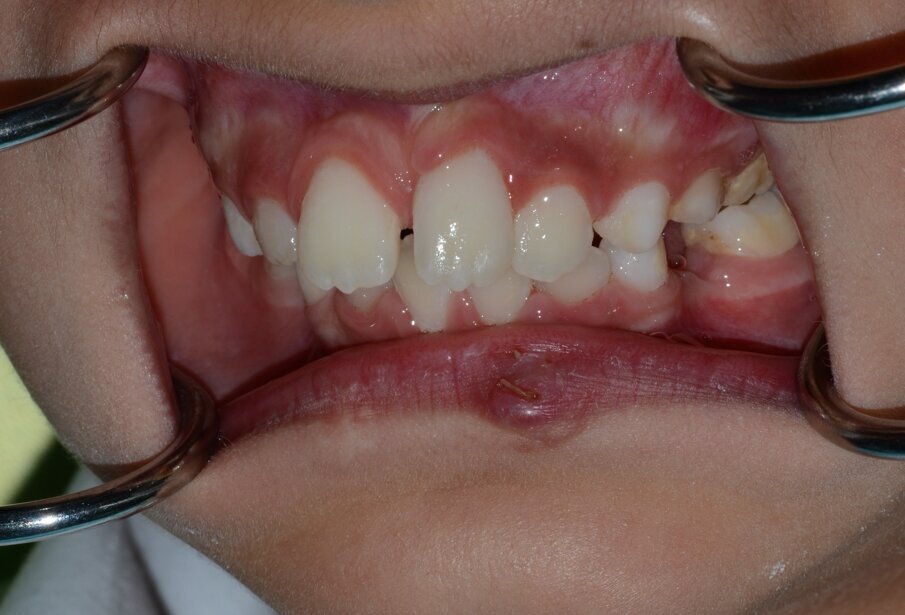

Within the hour, tooth 21 was gently replanted into the socket (Figure 6) and a flexible 0.5mm wire/composite passive splint of teeth #12, 11, 21, 22 was secured (Figure 7). We sutured the lacerated lower lip in multiple layers (mucosa, deep and superficial) using Vicryl® (Sizes 40 and 60) resorbable fine sutures (Figure 8 and 9). This took place after thorough debridement of the wound with physiological saline. Care was taken to assure alignment of the lip’s vermilion involved in the laceration.

Figure 9. Immediate post suturing. Notice the wound margins had been aligned so the vermilion was continuous.

Figure 10b: The clinical appearance following a second trauma incident that happened within two hours of fitting the dental splint.